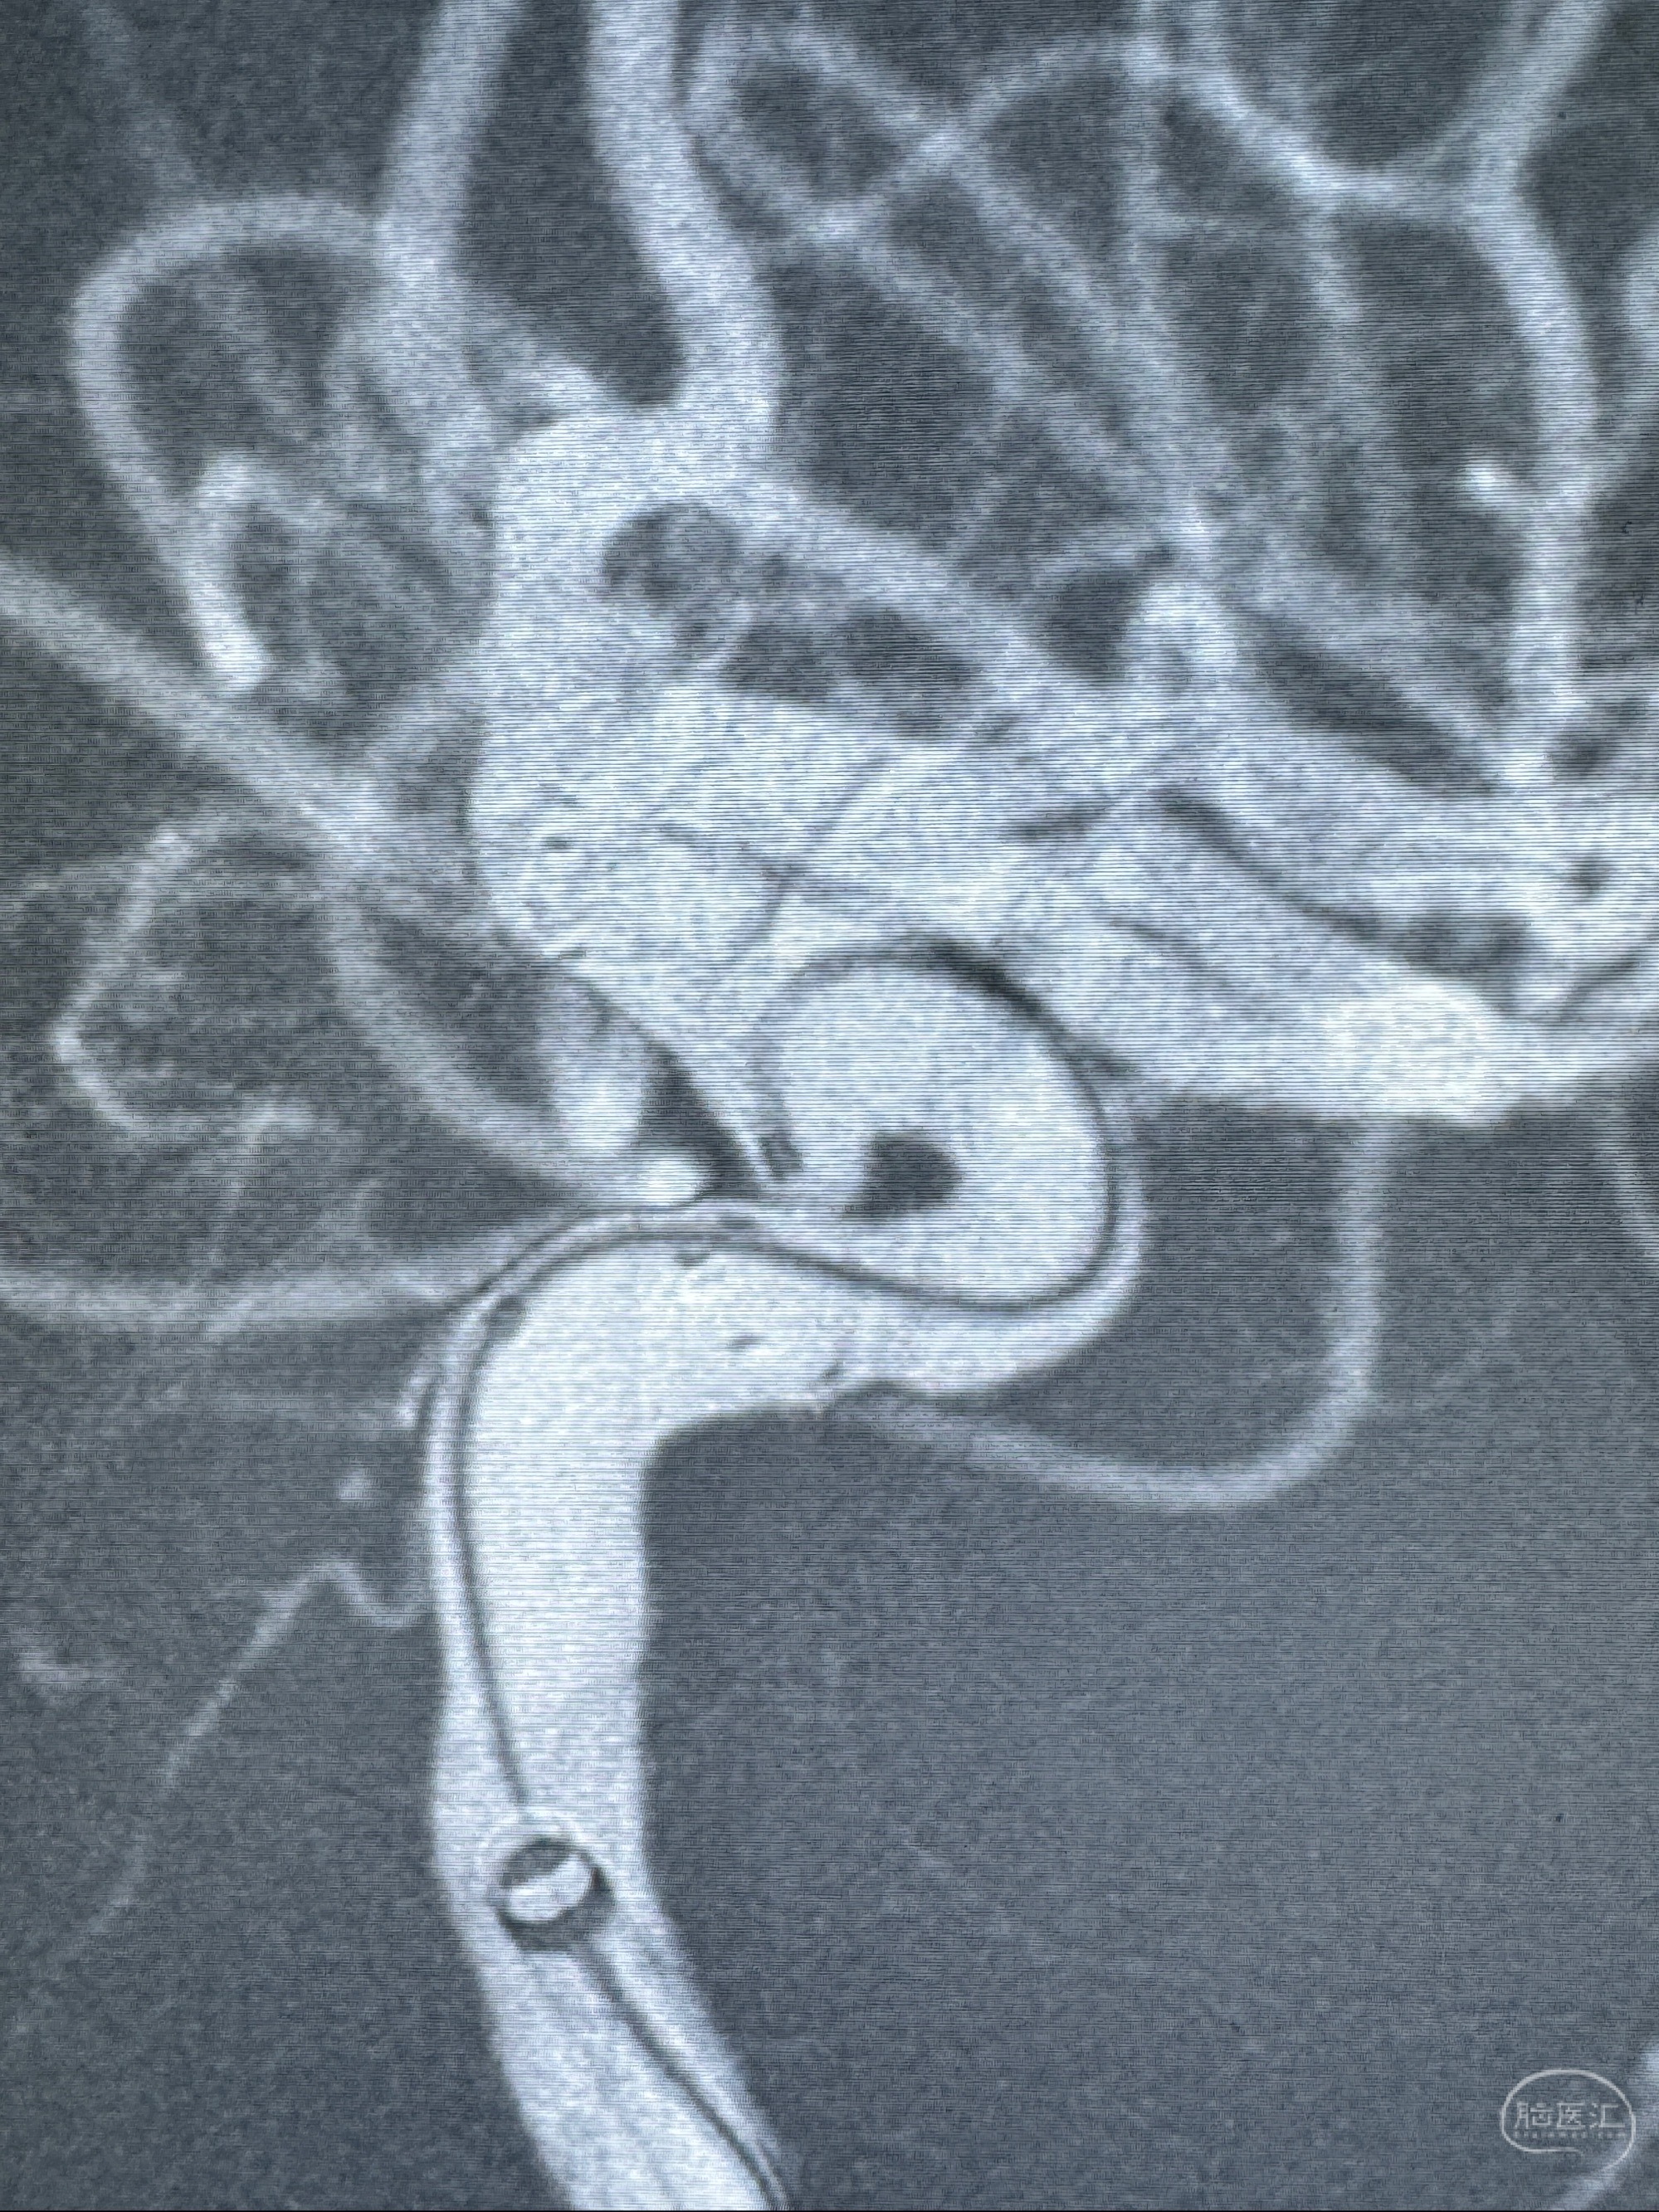

2023-11-13DSA:左侧颈内动脉眼动脉后壁动脉瘤

2023-11-29全麻下行NeuroformEZ4.5-20mm支架辅助栓塞

术后即刻CT